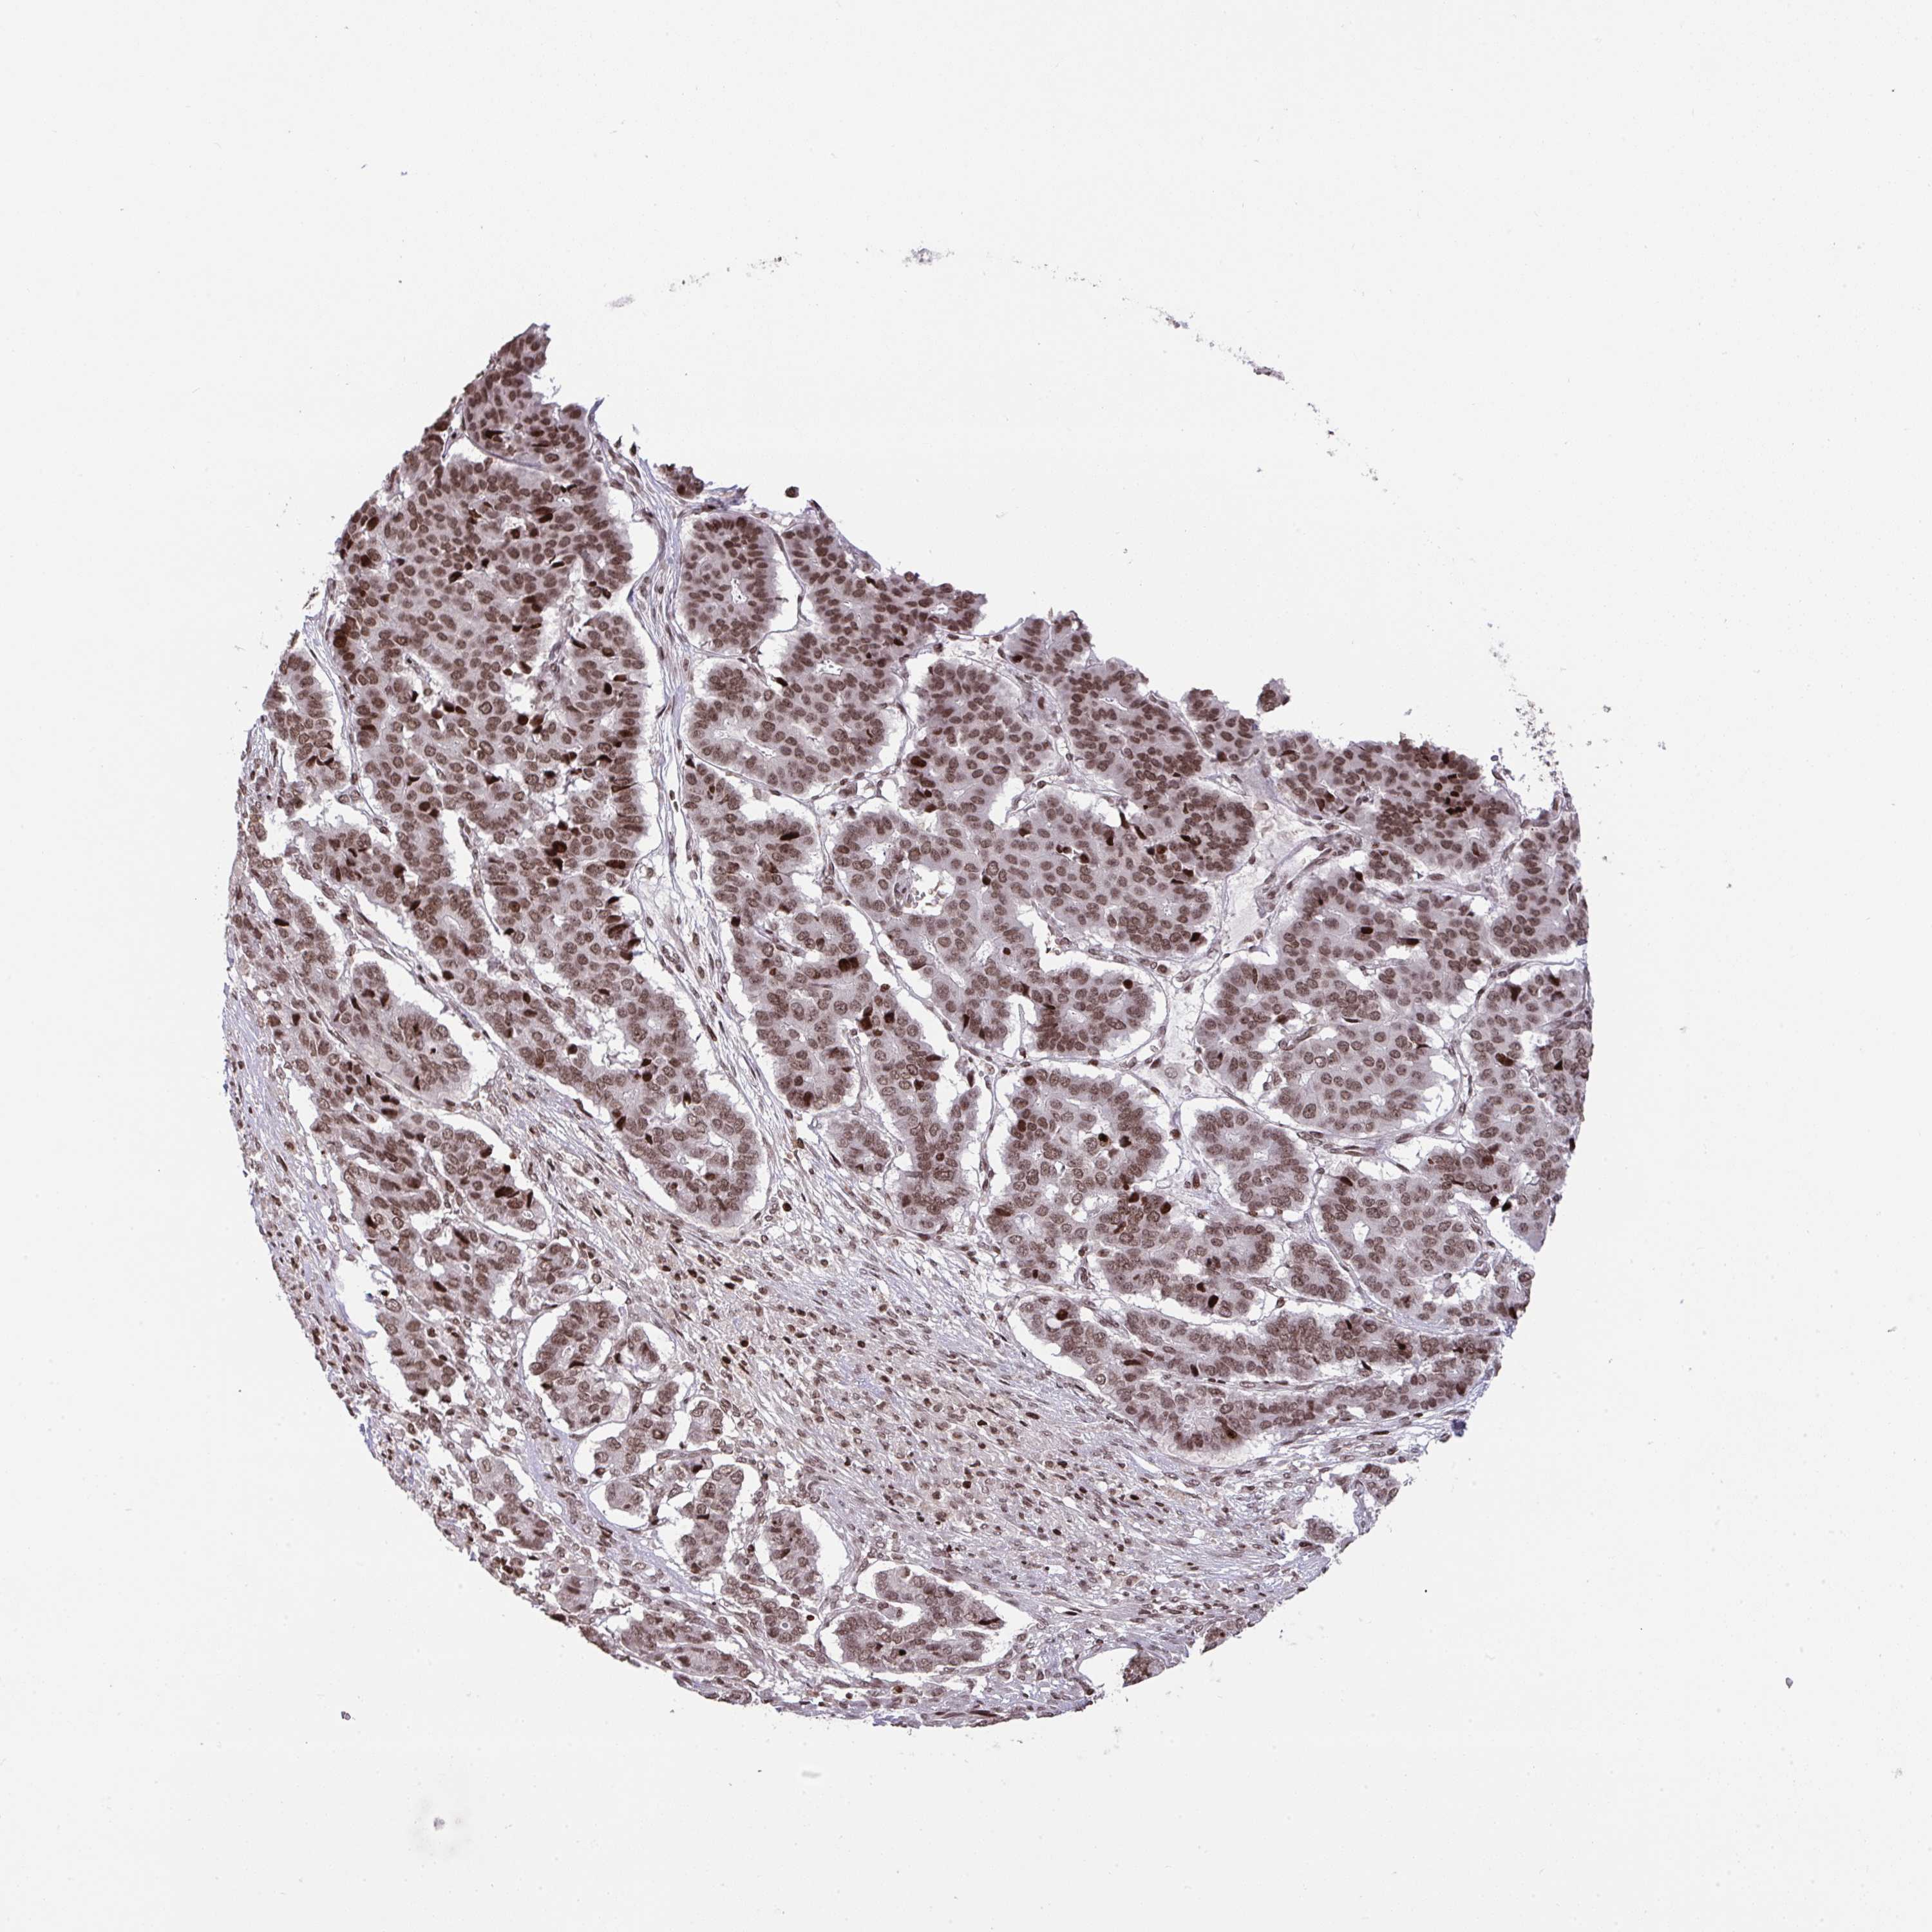

PANCREATIC CANCER - Protein expressioni

A mouse-over function shows sample information and annotation data. Click on an image to view it in a full screen mode. Samples can be filtered based on level of antibody staining by selecting one or several of the following categories: high, medium, low and not detected. The assay and annotation is described here.

Note that samples used for immunohistochemistry by the Human Protein Atlas do not correspond to samples in the TCGA dataset.

Antibody stainingi

Antibody staining in the annotated cell types in the current human tissue is reported as not detected, low, medium, or high, based on conventional immunohistochemistry profiling in selected tissues. This score is based on the combination of the staining intensity and fraction of stained cells.

Each image is clickable and will lead to virtual microscopy that enables deeper exploration of all samples and also displays staining intensity scores, fraction scores and subcellular localization as well as patient and tissue information for each sample.

Antibody HPA059850

Staining

High

Medium

Low

Not detected

Intensity

Strong

Moderate

Weak

Negative

Quantity

>75%

75%-25%

<25%

None

Location

Nuclear

Cytoplasmic/membranous

Cytoplasmic/membranous,nuclear

Adenocarcinoma, NOS